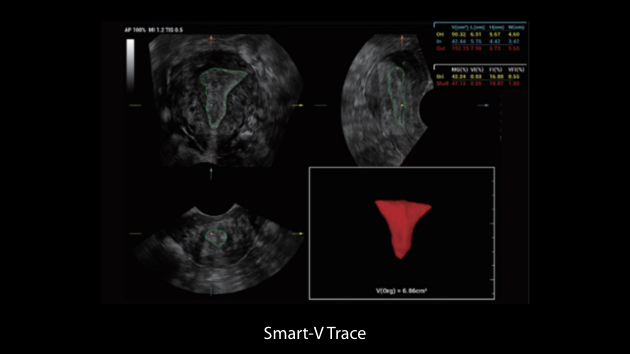

ZST+ ???? ???? ??? ???? ??? ?????. ??? ????? ??? ? ???? ?? ??? ?? ????? ?????. ?? ???, ?? ???, ?? ??? ?? ?? ?? ??? ??? ???? ???? ??? ?? ??? ?? ???? ?? ??? ?? ??? ?????.